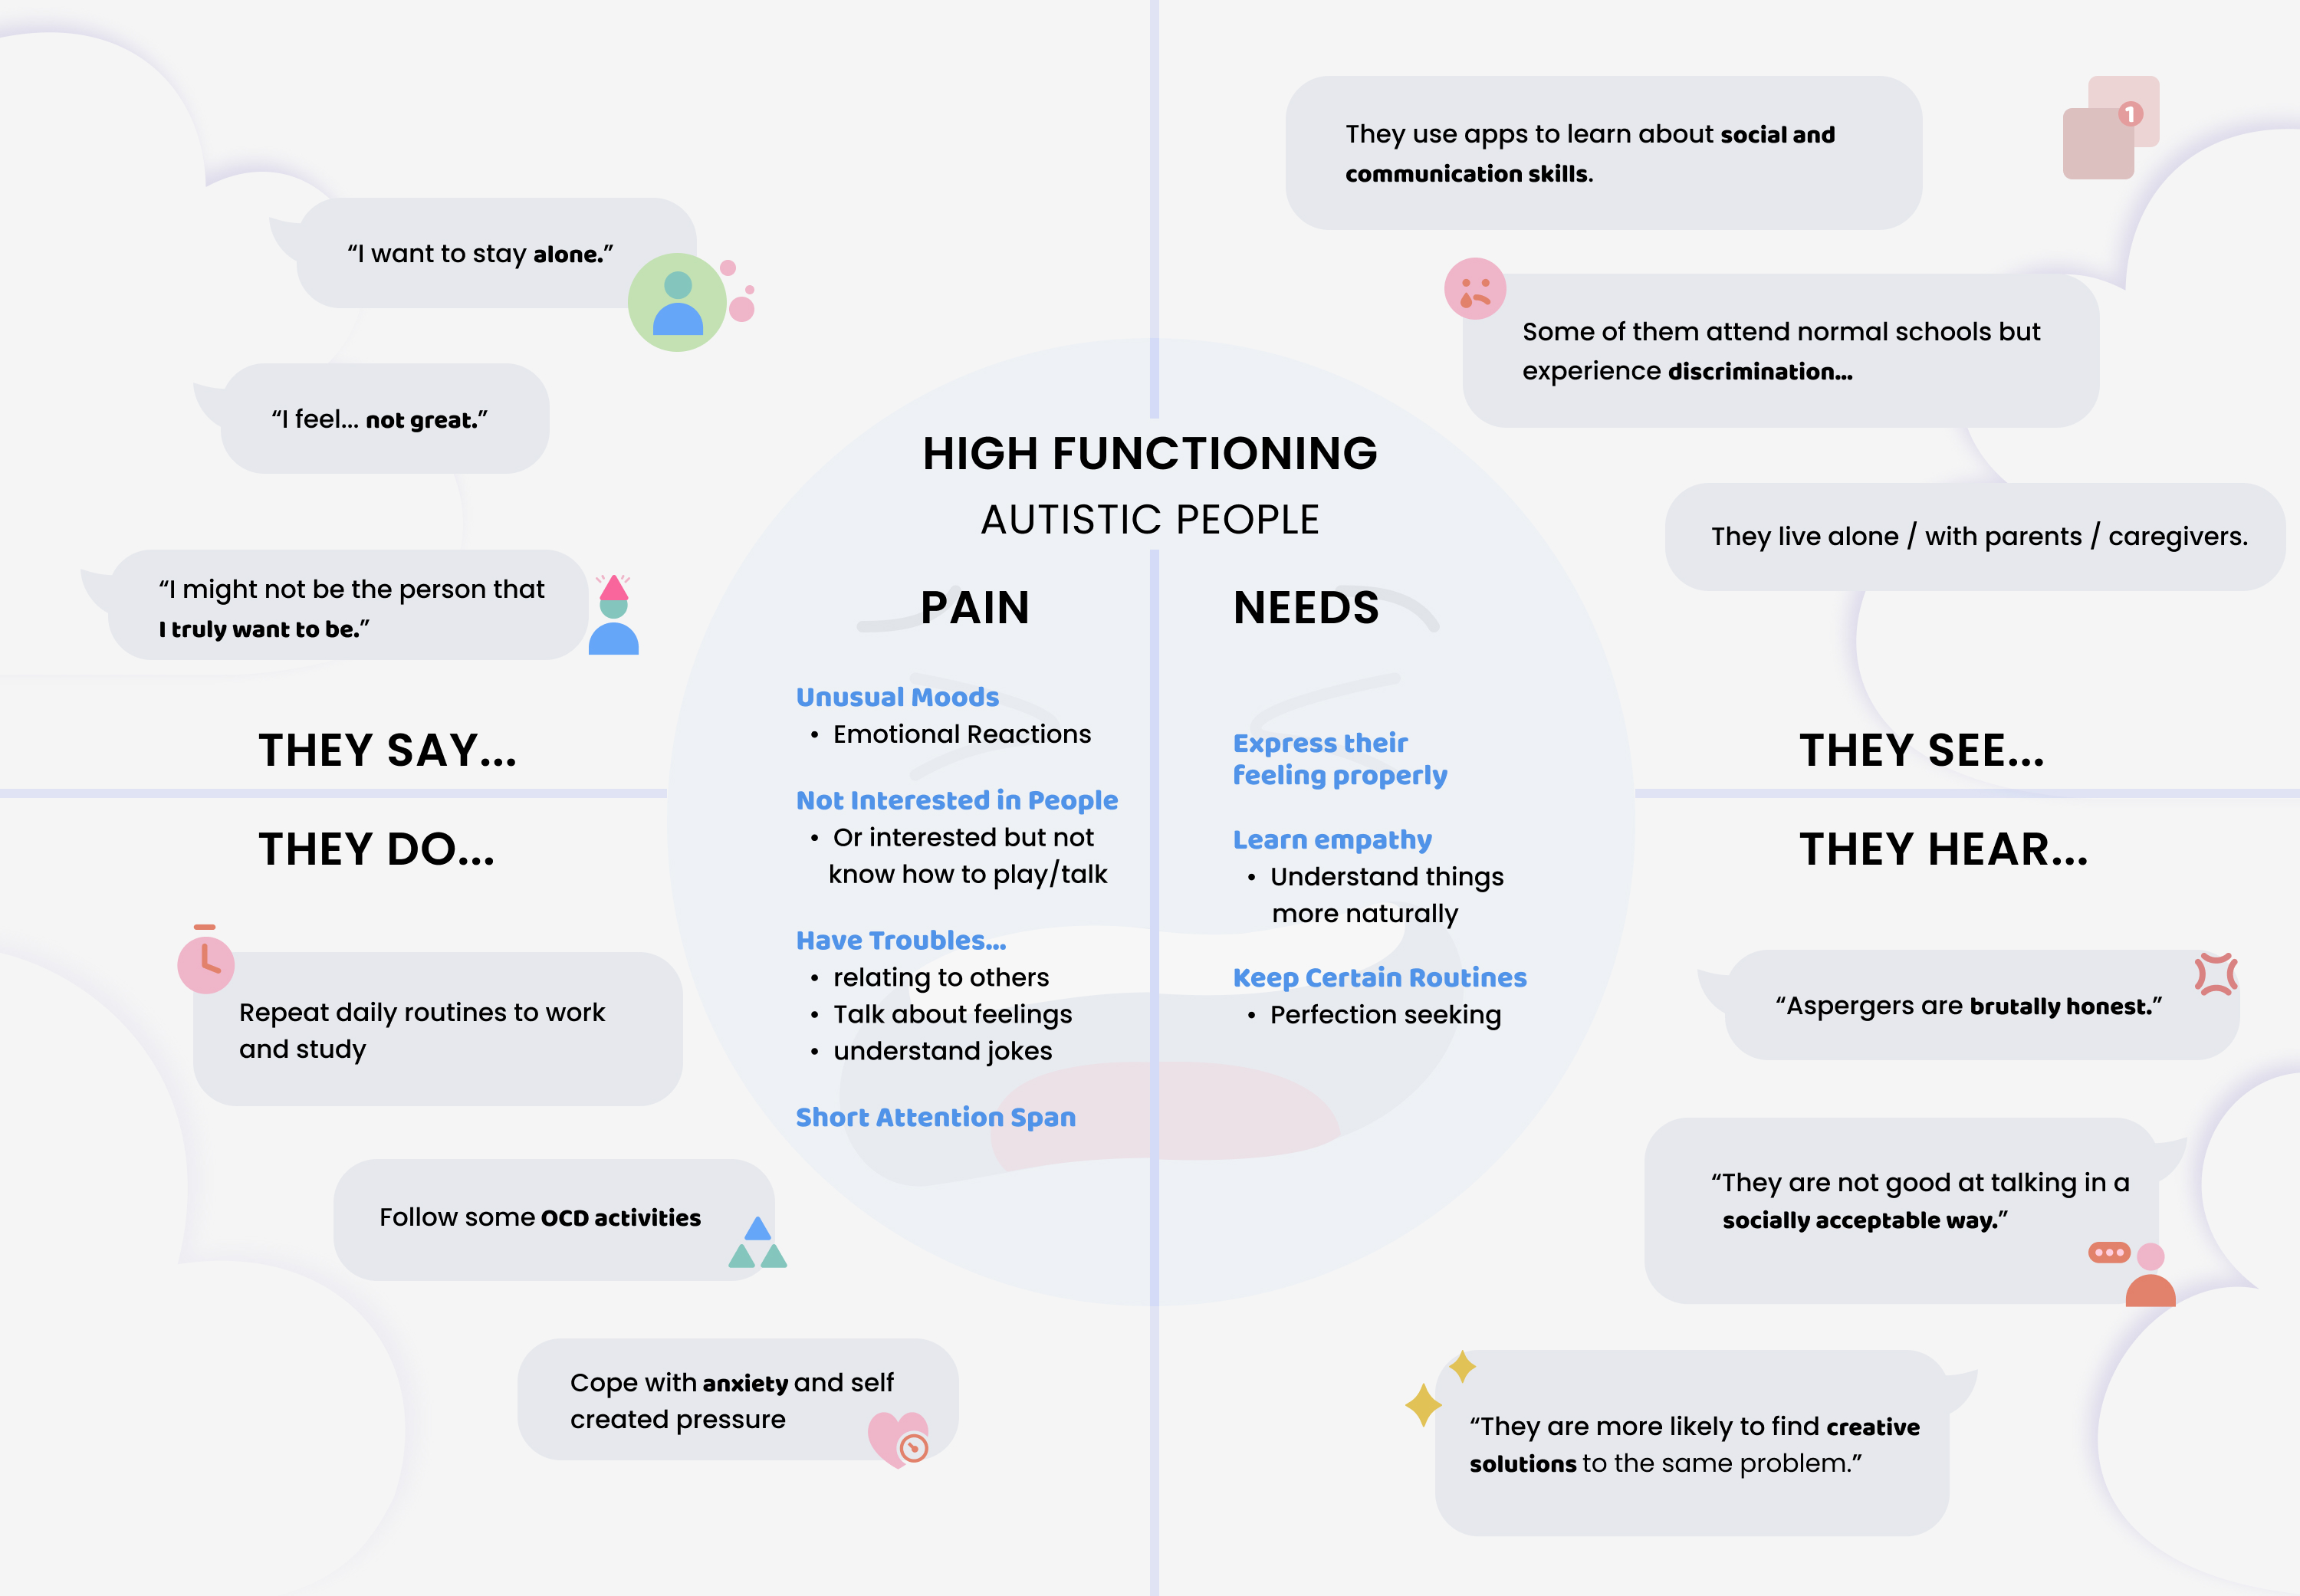

3. Coping with Anxiety and intense emotions 1 is a big challenge for most autistic people. Some of them can feel the emotion but has difficulties naming them, and some of them have hyper sensitivity to stimuli.

I did an empathy map to reflect wants and needs for High functioning autistic kids. I found many of them have pattern seeking behavior, and finding patterns makes them feel safe 2 .